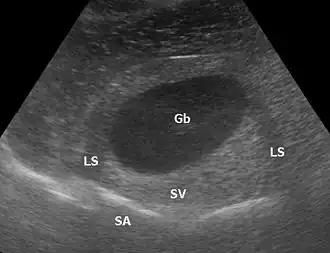

Gb Gallenblase, LS lateral shadowing, SA distale Schallauslöschung hinter dem stark reflektierenden Zwerchfell, SV distale Schallverstärkung

Bei der Bilderzeugung mittels Ultraschall kann es zu Artefakten (Bildfehlern) kommen, die nicht durchweg als störend gelten, sondern auch zusätzliche Gewebe- bzw. Materialinformationen liefern können.

Ein häufiges Artefakt ist die Abschattung (distale Schallauslöschung) hinter stark reflektierenden Objekten mit einer vom übrigen Gewebe stark abweichenden Impedanz wie Knochen, Luft oder Konkrementen (Ablagerungen). Bei nahezu senkrechtem Schalleinfall gibt es ein starkes Echo, bei schrägem Einfall nicht.

Eine distale Schallverstärkung ist ein übermäßig hell dargestelltes Gewebe hinter (distal) einer Struktur, die wenig dämpft. Allgemein wird, um die Dämpfung des Gewebes auszugleichen und zum Beispiel Lebergewebe über die gesamte Tiefe homogen darzustellen, mit Hilfe der time gain compensation oder auch depth gain compensation, tiefer liegende Signale zunehmend verstärkt. Zum Beispiel bei einer Gallenblase in der Leber ist das Lebergewebe deutlich heller als das restliche Lebergewebe, weil Galle weniger dämpft als Lebergewebe, aber das Gewebe hinter der Gallenblase mit dem gleichen Verstärkungsfaktor aufgehellt wird wie das umliegende Gewebe.

Bei kreisförmig geschnittenen Objekten können die Randstrahlen weggespiegelt werden; dem Bild fehlen dann die Randstrukturen und es kommt zu Abschattungen (engl.: lateral shadowing).